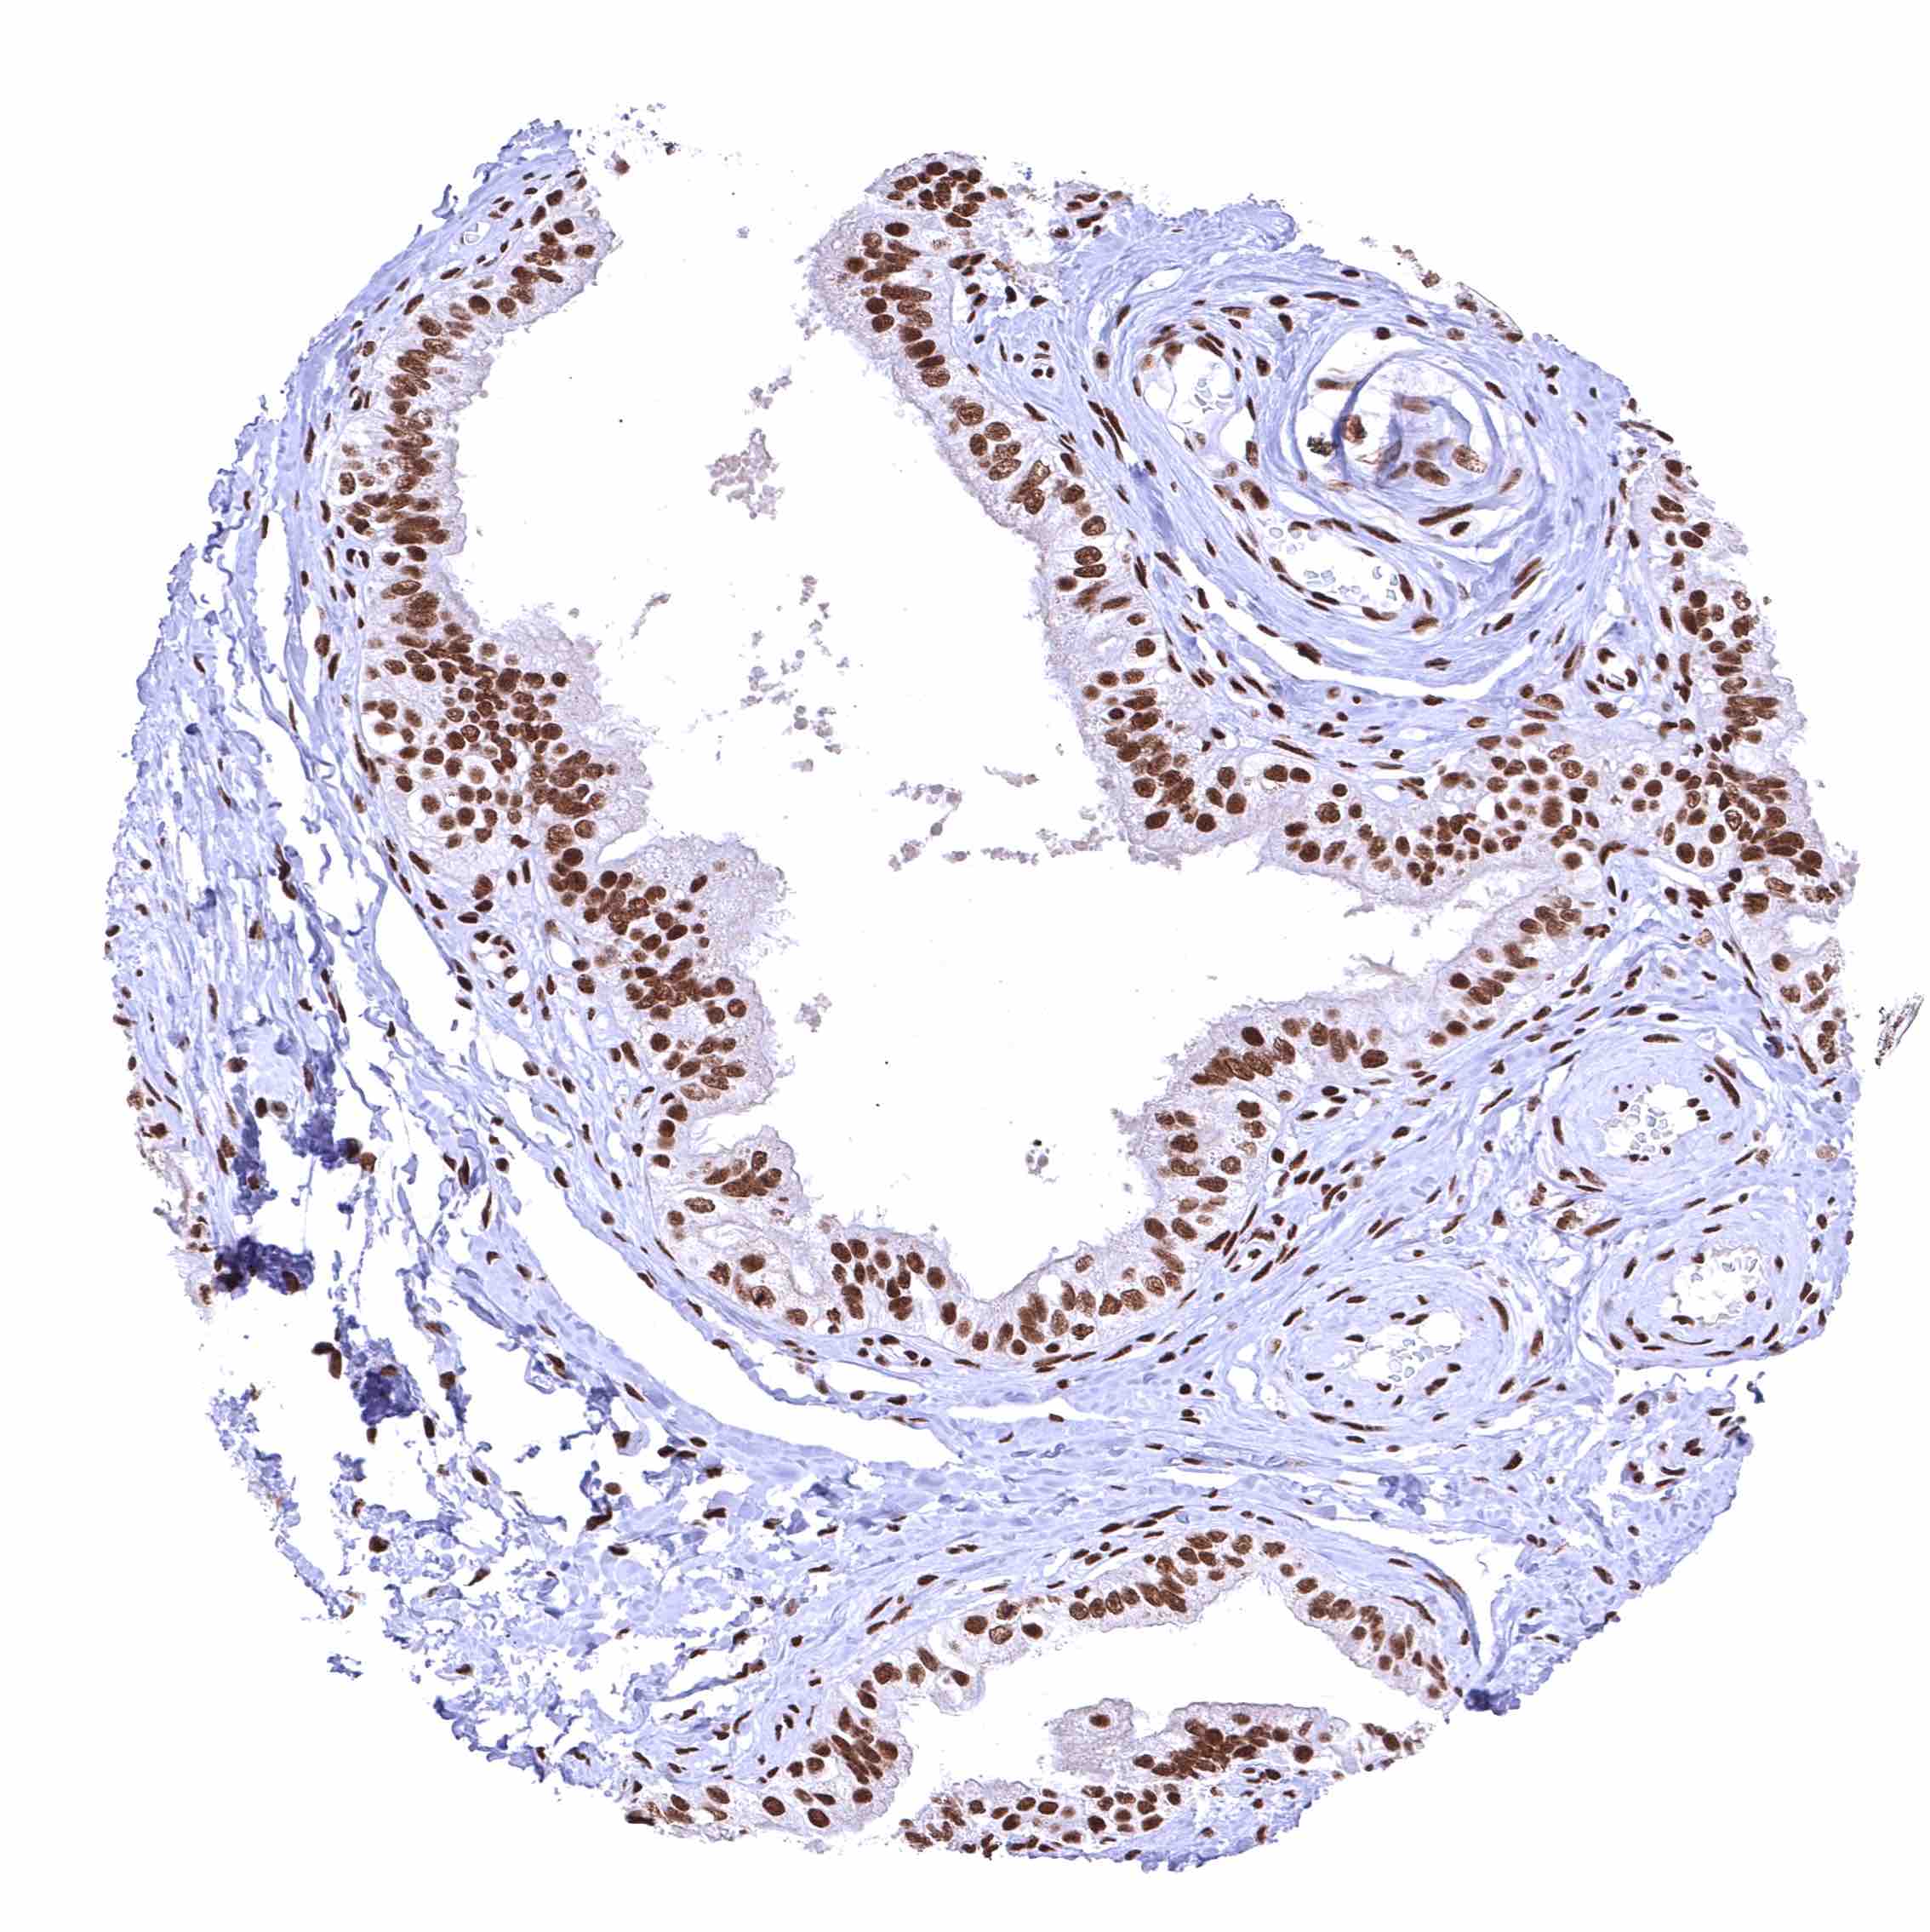

BRD4 antibody [HMV4275] HistoMAX™

Esophagus, squamous epithelium – Distinct nuclear BRD4 staining of squamous epithelial cells with a slight decrease of the staining intensity towards the most superficial cell layers.